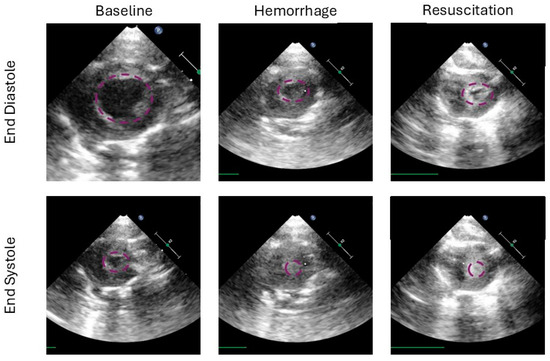

Fractional area change is the 2-dimensional equivalent to the commonly assessed left ventricular ejection fraction. FAC aims to assess left ventricular function, while CO assesses both ventricles combined. There was no significant correlation between independent variables and FAC at end-experiment in survivors, p = 0.56, 0.6, and 0.67 for hemorrhage time, down time, and FiO2; Figure 5.

Figure 5. (A). Fractional area of change (FAC) at end-experiment in those who survived is demonstrated in a heat map for 21% FiO2. This does not include animals who did not survive, e.g., the MAP was <30 mmHg 2 h after beginning resuscitation. (B). The same map demonstrates values in the presence of 40% FiO2.